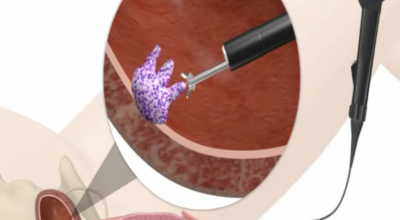

방광암 치료법은 경요도 절제술을 하게 되는데요. 이 후 종양의 개수나 크기, 재발 기간 등에 그렇기 때문에 항암제를 주입하는 등 여러가지 치료를 하게 되는데요. 상황에 그렇기 때문에는 방광 적출술이 필요할 수 있고, 재발이 잦기 때문에 방광암 치료법을 시행하면서도 주기적인 추적 검사를 해야 합니다.